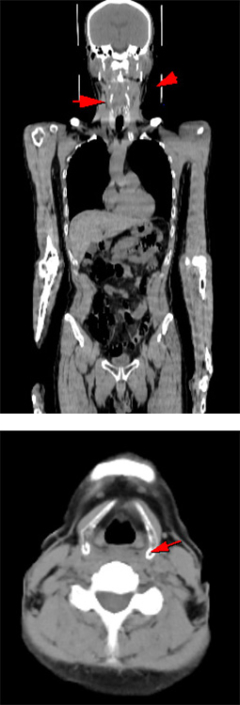

⑥CTやMRIなどと組み合わせるとより詳しくがんがわかります

CTやMRI検査は、体の中の組織や細胞の「かたち」を画像でとらえ、周囲臓器との関係をみることによってその異常を見つけます。これに対しPET検査は、細胞の「活動状態」を画像でとらえる検査法です。

PET検査を組み合わせることで、違った種類の情報が加わり、CTやMRIなどの検査だけでは見つかりにくかったがんが、発見しやすくなります。

またPETはCTやMRIに比較して空間分解能が低く異常が発見されても病気がどこにあるかはっきりわからない場合があります。そこでCTやMRIなどと合成(フュージョン)すると、病変部位の解剖学的な「形や大きさ」を正確に把握することができます。

▲早期右乳癌